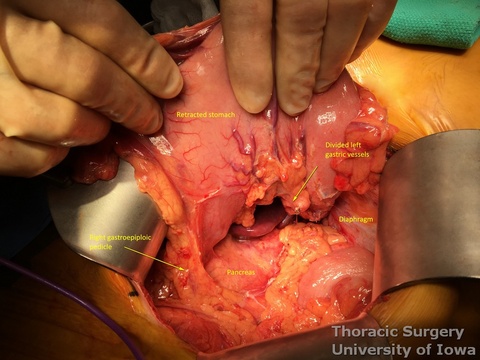

- Peritoneum is incised, protecting the splenic artery and pancreas. 1-2 mm posterior gastric artery, originating from the proximal splenic artery fs present (in half of individuals) and is divided.

- Once the stomach is mobilized and reflected anteriorly, the left gastric vascular pedicle is identified and dissected close to the origin for adequate lymphadenectomy. Care is taken to not injure splenic artery and pancreas.

- Left gastric vessels are divided with an endoscopic linear cutting stapler proximally, including all adjacent lymph nodes in the specimen.

- Adequate mobility of the fully mobilized stomach is assured by the ability to bring the pylorus towards the hiatus.